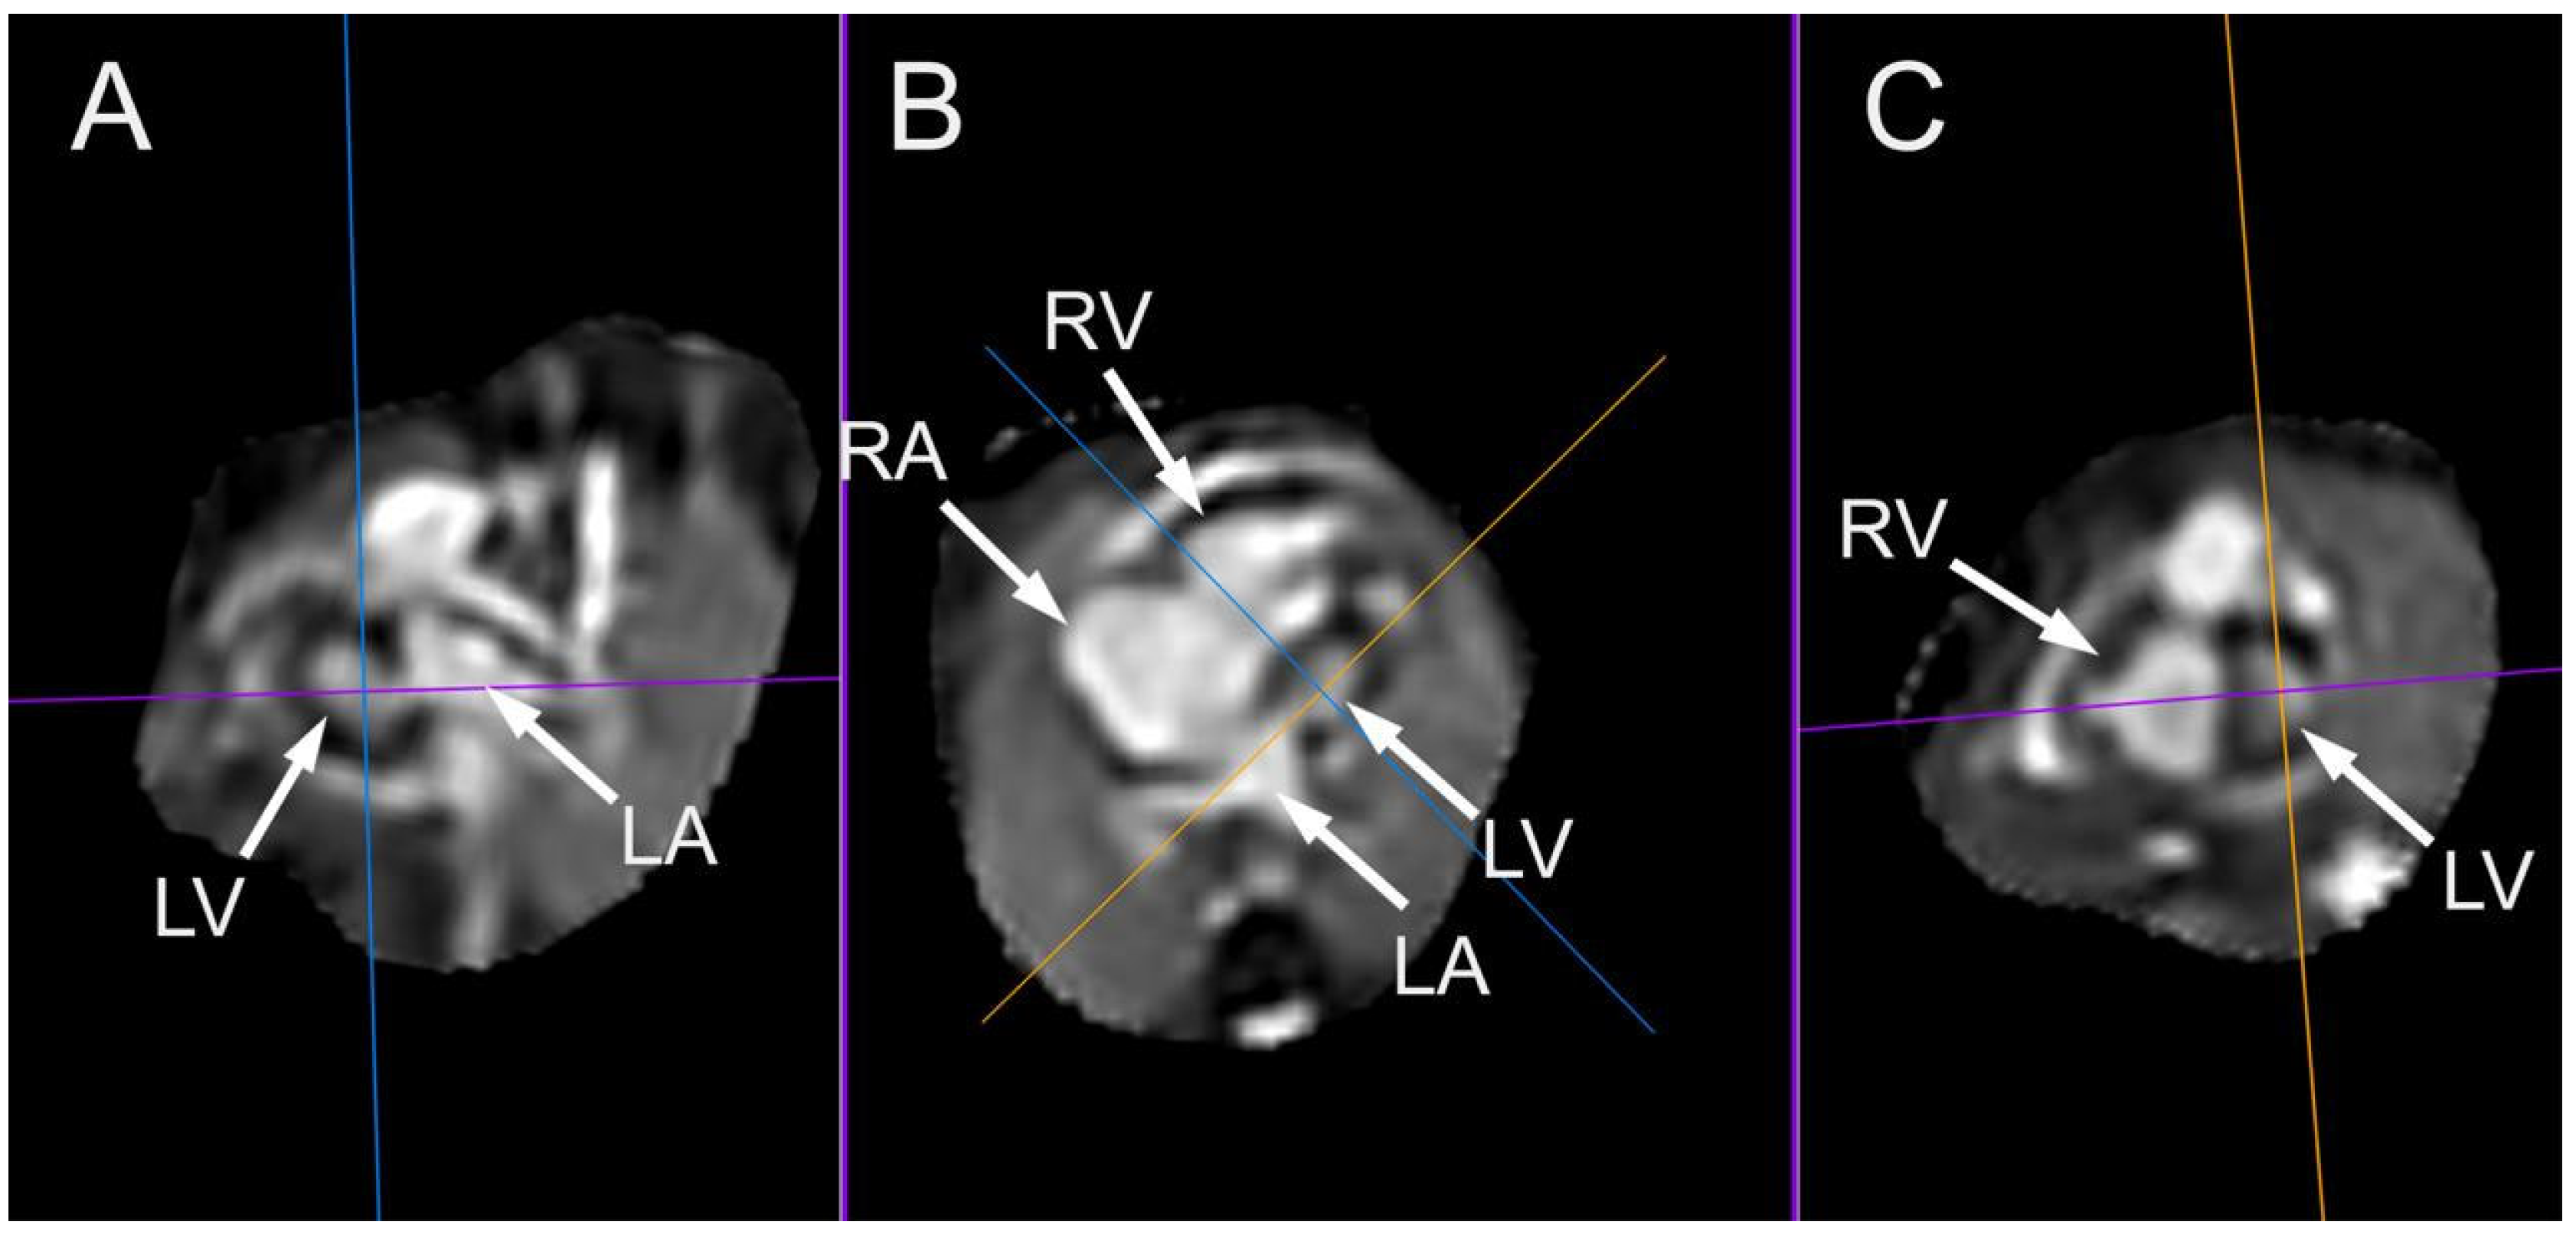

- Goncalves LF, Lindblade CL, Cornejo P, Patel MC, McLaughlin ES, Bardo DME. Contribution of fetal magnetic resonance imaging in fetuses with congenital heart disease. Pediatr Radiol. 2022, 52, 513–526.

- Rubert NC, Jategaonkar G, Plasencia JD, Lindblade CL, Bardo DME, Goncalves LF. Four-dimensional fetal cardiac imaging in a cohort of fetuses with suspected congenital heart disease. Pediatr Radiol. 2023, 53, 198–209.